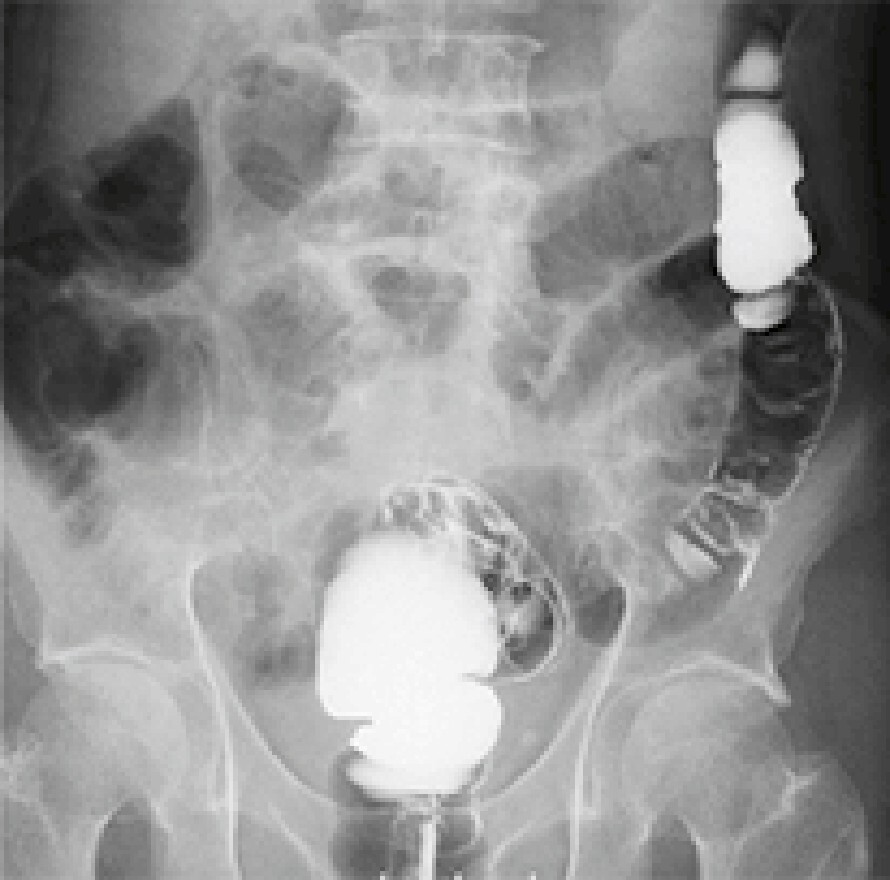

デジタルX線テレビシステム

従来より高画質で低線量なデジタルX線テレビシステムです。透視検査では人体の透過像を動画で観察し、X線写真を撮影します。消化器から整形外科まで幅広い領域の画像検査に対応しています。